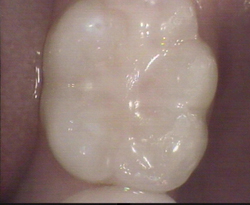

Top of back tooth

Restored